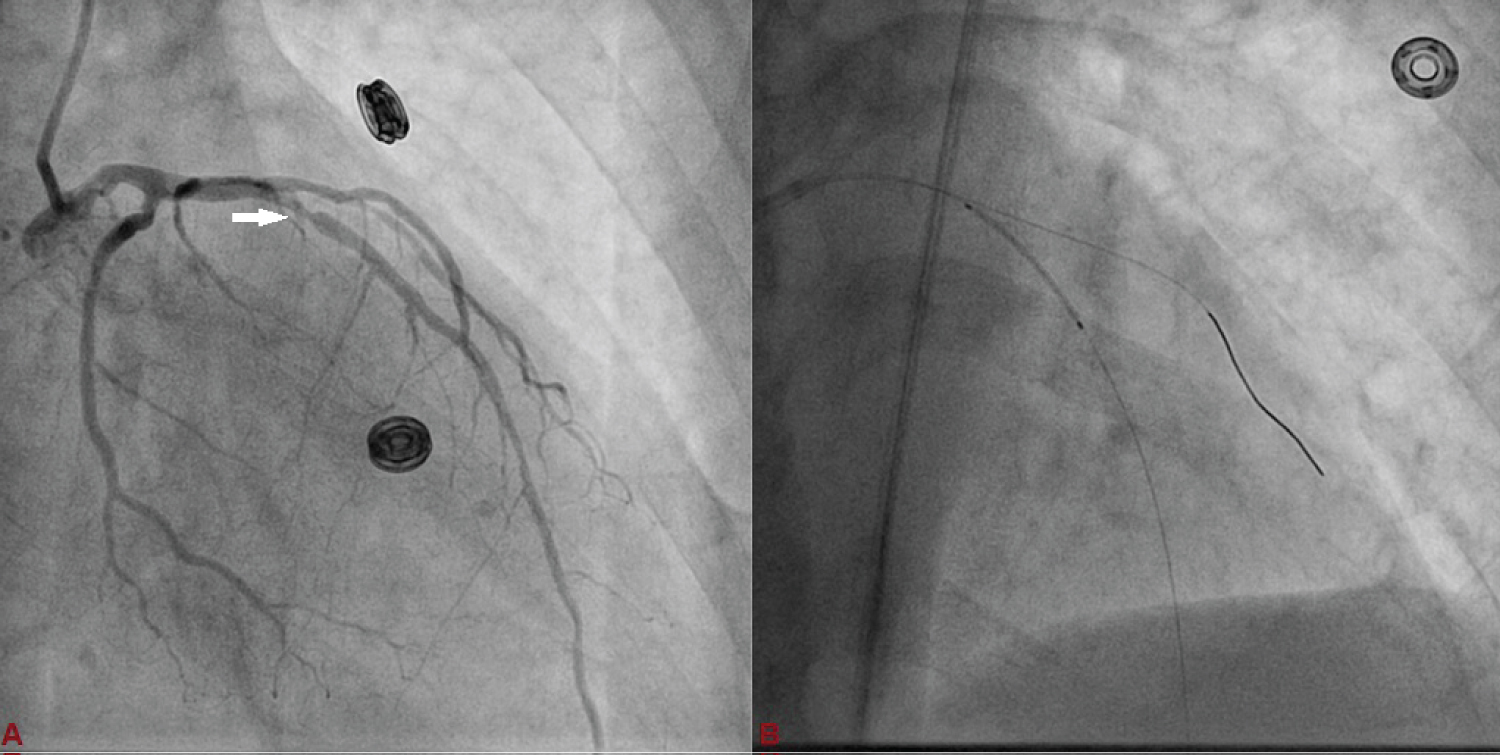

A 75-year-old diabetic and hypertensive male presented with chest heaviness with sweating of 6 hours duration. An electrocardiogram showed marked ST elevation in V1-V6. Routine haemogram and biochemistry was normal except deranged renal function with serum creatinine of 3.3 mg%. His body weight was 68 kg. Echocardiography revealed mild concentric left ventricular hypertrophy, regional wall motion defect in left anterior descending territory (LAD), and impaired systolic function with an ejection fraction of 40%. His coronary angiogram was done through transfemoral approach after proper consent revealing critical lesion with 90% stenosis in mid left anterior descending (LAD) artery just after large diagonal branch, normal left circumflex territory, and right coronary artery (Figure 1 and Figure 2). The coronary angiogram was completed using 9 ml of contrast. The contrast used was iodixanol which is an iso-osmolar contrast agent. Primary PCI was planned subsequently. Intravenous heparin (100 U/Kg) was administered. Based on all the baseline factors, it was a high risk PCI carrying a profound risk of CIN. To minimize the risk of CIN, intravenous normal saline infusion was started. Prior to PCI, initial angiogram with same angle of projection was uploaded to the monitor for PCI guidance. Left main artery was engaged with 6F extra backup guiding catheter (EBU; Medtronic, USA) which was confirmed by entry of the runthrough wire (Terumo, Japan) into the coronary artery. An exaggerated curve was created to facilitate the wiring of LAD. Additional runthrough wire was placed in first diagonal branch (D1) based on the previous angiogram (Figure 3). The side branch wire served as an important landmark to guide PCI and to protect the side branches as well. The balloon was positioned just after D1 which was used as a landmark for proximal end for stent placement. Lesion was gradually predilated with 2 × 10 and 2.5 × 10 pantera leo semi compliant balloons (Biotronik, Germany). 3 × 23 mm Endeavour Resolute (Zotarolimus eluting stent; Medtronic, USA) stent was positioned across the lesion keeping the proximal end at the crossing of LAD and D1 wire which was serving as the origin of D1 (Figure 3). It was deployed at 13 atm pressure (Figure 4). As it was not fully expanded, it was serially post dilated by 3 × 10 and 3.5 × 10 non-compliant Minitrak balloon (Abott, USA) at 24 atm pressure. The stent apposition was checked under stent boost. After confirmation of stent optimization with stent boost, final angiography with 4 ml contrast injection revealed successful results (Figure 5). Therefore, PCI was completed using 13 ml of contrast. He was clinically stable for 2 days without CIN (Serum creatinine 3.5 mg/dL). She was discharged 2 days after PCI with appropriate drugs and has been uneventful.

Figure 1: Left anterior descending (LAD) artery revealing critical lesion with 90% stenosis in mid just after large diagonal branch (D1), and normal left circumflex artery. (A: Antero-posterior view with caudal angulation; B: Antero-posterior view with cranial angulation). View Figure 1

Figure 3: A) Basal angiographic view of left system used as anatomical reference to mark position of LAD and D1; B) 3 × 23 mm Endeavour Resolute stent was positioned across the lesion keeping the proximal end at the crossing of LAD and D1 wires which was serving as the origin of D1. View Figure 3